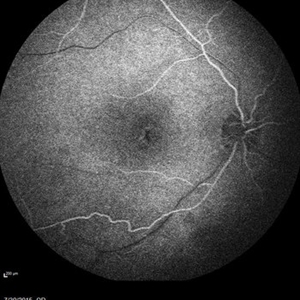

Retinal Dystrophy of 24-Year-Old Male/ Red Free OD

Nov 25 2015 by Zach Dupureur

Fluorescein angiography of a 24-year-old male. Juvenile retinoschisis on OCT. FA shows outer retinal staining. Could be associated with Goldman Farve Syndrome.

Photographer: Zach Dupureur OCT-C

Imaging device: Heidelberg Spectralis

Condition/keywords: Goldmann-Favre Syndrome, juvenile retinoschisis, retinal dystrophy